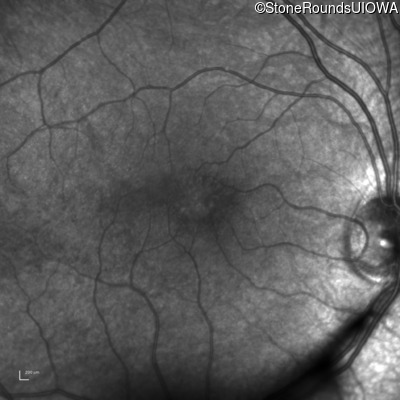

Infrared Fundus Photograph - Left - 20/40 +2

Exemplar